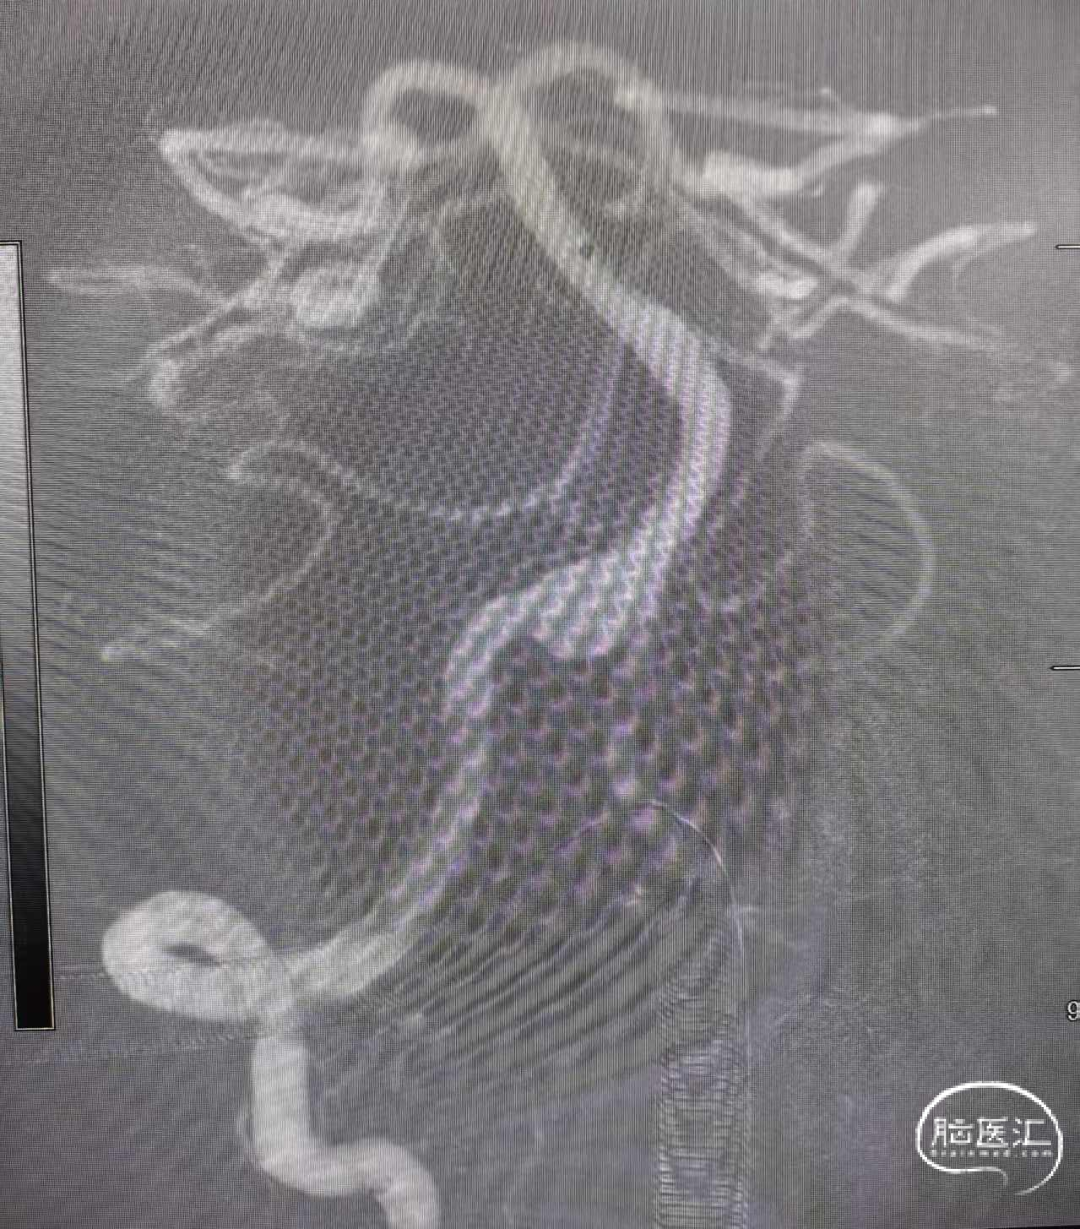

术前3D影像:

DSA正侧位造影显示:右侧椎动脉V4段夹层动脉,瘤颈约8mm,血管直径约3.5mm。

造影后发现右侧椎动脉夹层动脉瘤,发生部位V4段,夹层远端累及汇合处,动脉路径较为迂曲。

影像显示导丝通过塑为“猪尾巴型”带Fastrack输送导管到达离动脉瘤远端大约20mm位置,以提供足够支撑。

输送支架到达输送导管远端,缓慢回撤输送导管使支架头端打开呈“V”型,整体回撤支架系统定位于动脉瘤远端约10mm处进行锚定。

支架释放到夹层处,采用“推挤技术”进行释放,促使夹层破口处金属覆盖率更高,有助于破口后期的修复与愈合。

当支架释放完毕时,即刻造影显示:支架整体完整覆盖夹层区域、支架打开充分、贴壁良好,夹层内血流滞留明显。

术后造影:

术后造影显示,囊内有明显的滞留、远端血流通畅。

患者治疗后4个月复查,3D成像清晰可见支架贴壁良好,载瘤动脉未见狭窄、夹层病变血管修复良好。